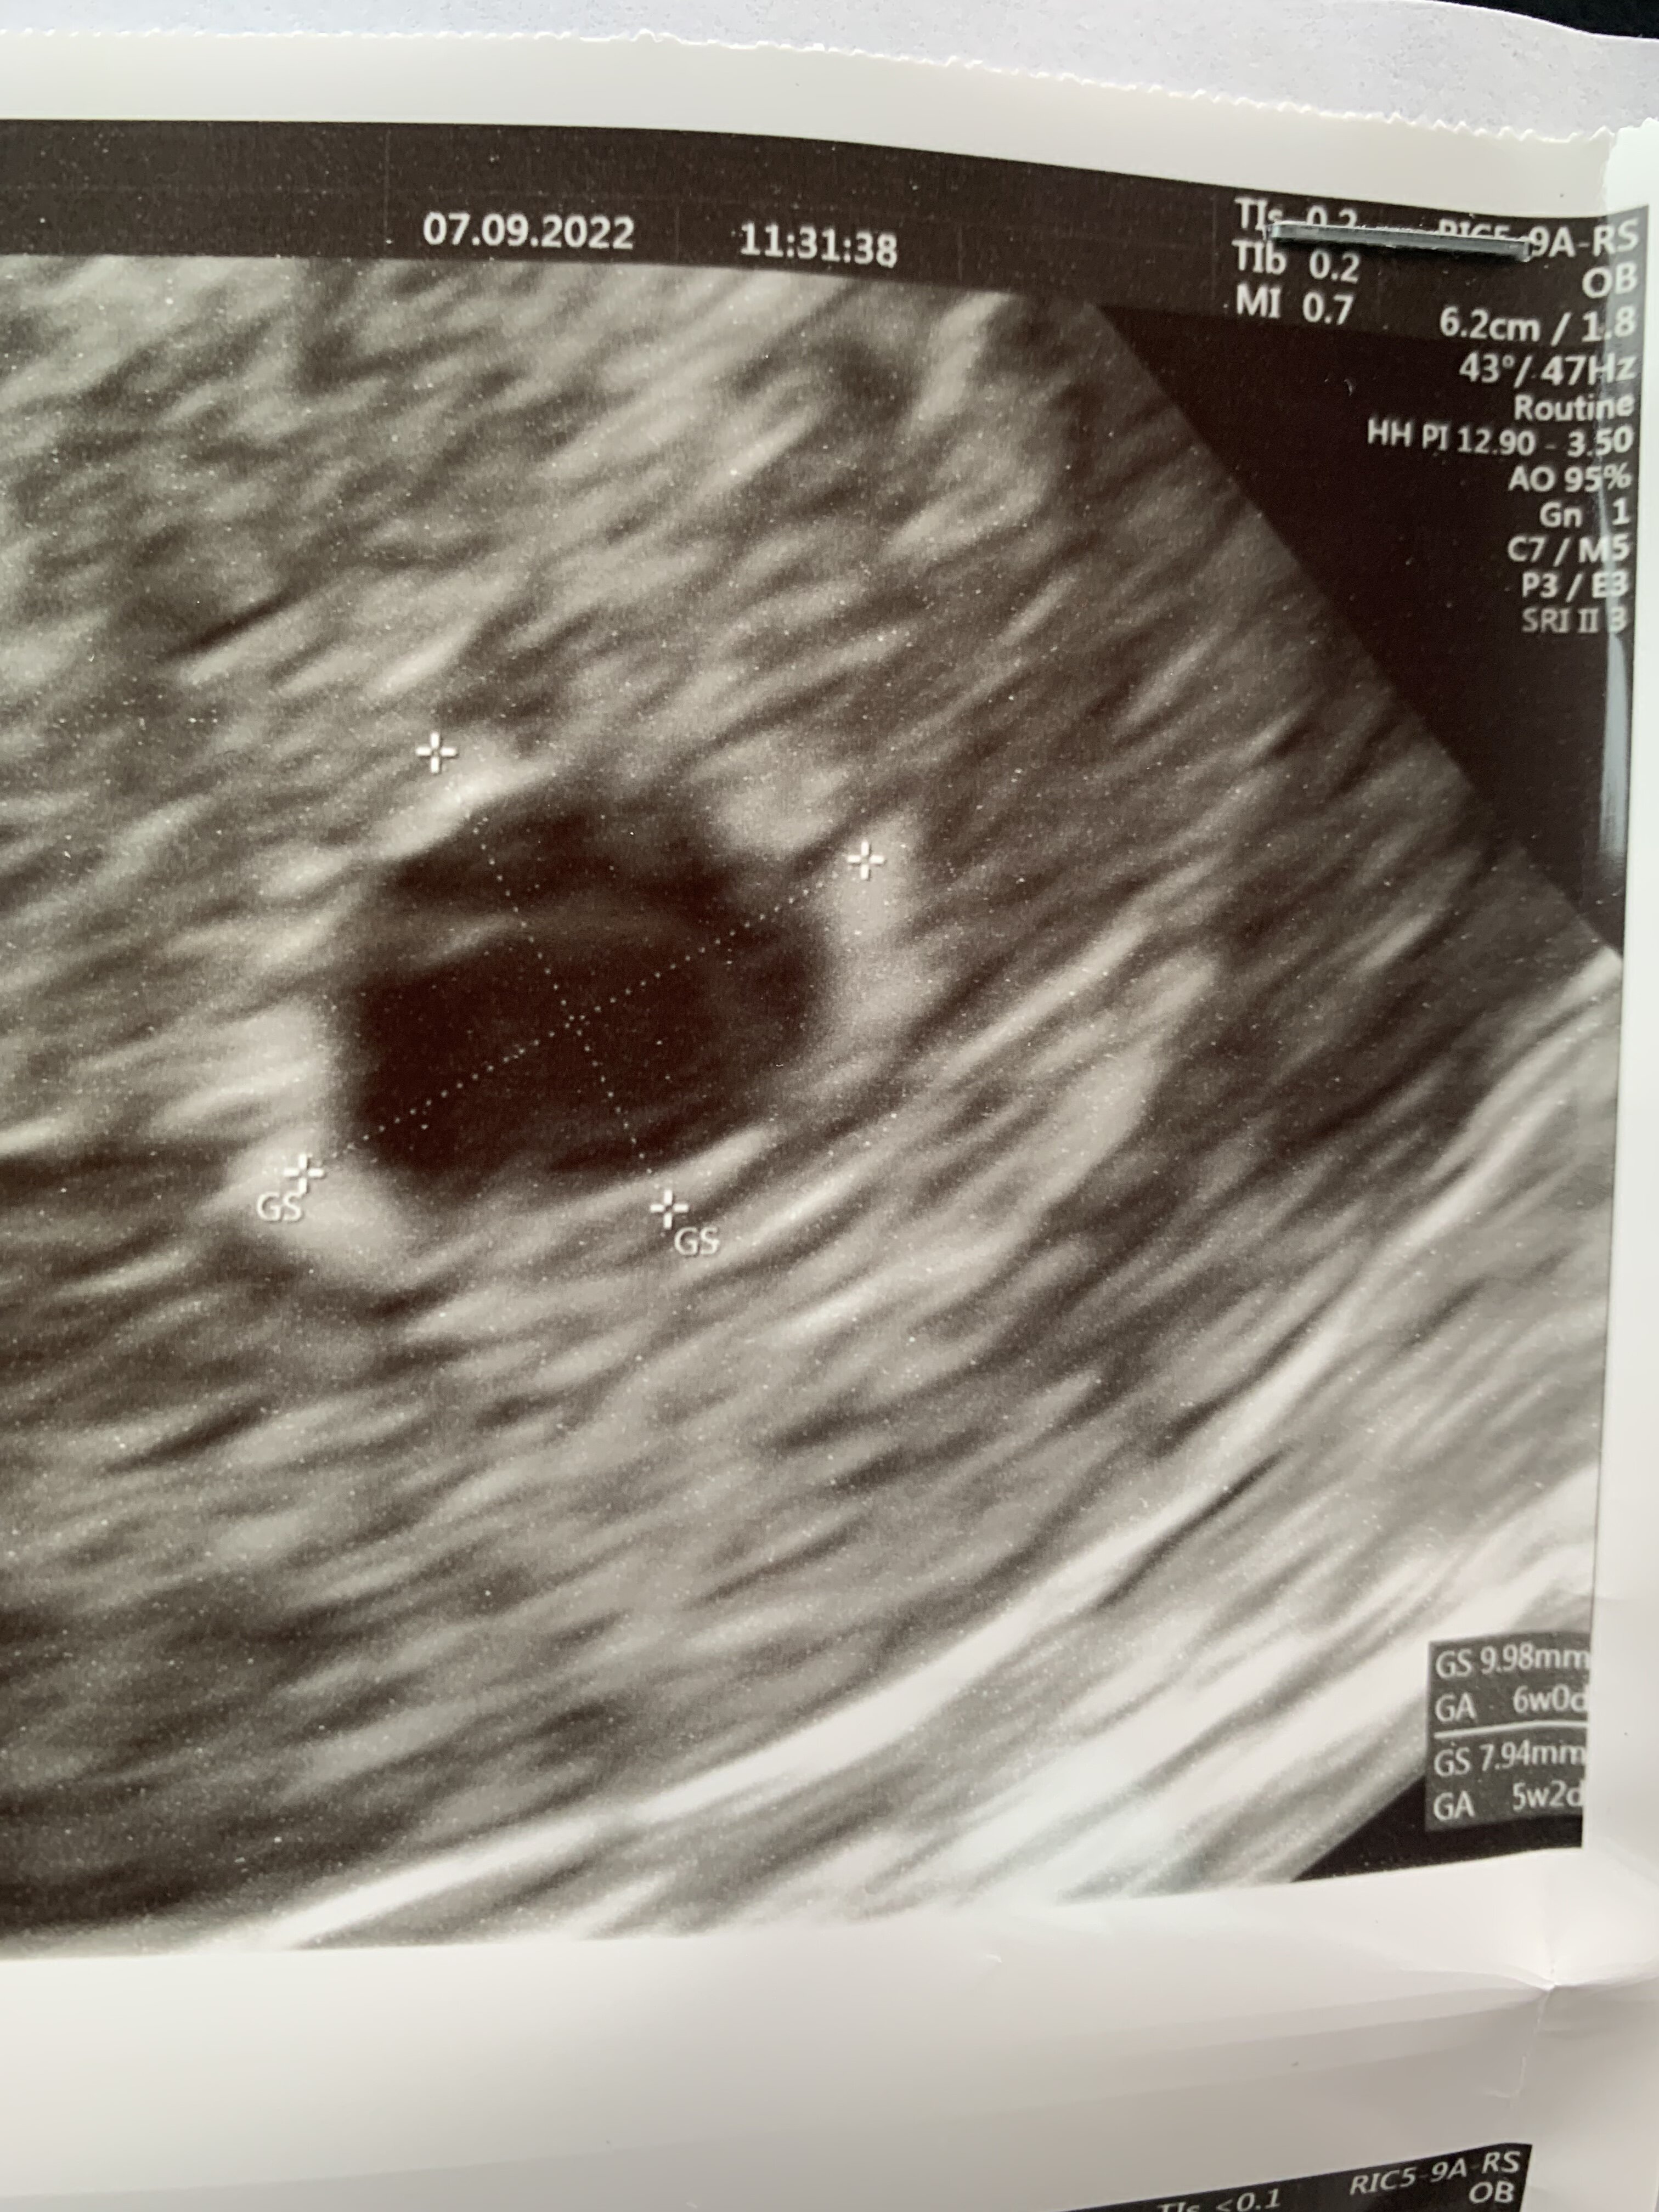

To są zdjęcia z tego USG 7 września? Jeśli lekarz nie widzi pęcherzyka żółtkowego to raczej my też go tam nie zobaczymy.Dziewczyny 7 wrześni byłam na pierwszym usg. W macicy widoczny pęcherzyk ciążowy o wym 9,98 x 7.94. Brak pęcherzyka żółtkowego. Następne usg 19 września. Ostatnia miesiączka 25 lipca. Przeważnie cykle 31-33 dni. Myślicie, że jest szansa że pijawi się jeszcze pęcgerzyk żółtkowy i zarodek. Na usg widać w pęcherzyku jakąś dziwna smuge. Beta w dniu usg ponad 4600

Ciężko stwierdzić , za wczesnienwtedy było na usg.Dziewczyny 7 wrześni byłam na pierwszym usg. W macicy widoczny pęcherzyk ciążowy o wym 9,98 x 7.94. Brak pęcherzyka żółtkowego. Następne usg 19 września. Ostatnia miesiączka 25 lipca. Przeważnie cykle 31-33 dni. Myślicie, że jest szansa że pijawi się jeszcze pęcgerzyk żółtkowy i zarodek. Na usg widać w pęcherzyku jakąś dziwna smuge. Beta w dniu usg ponad 4600